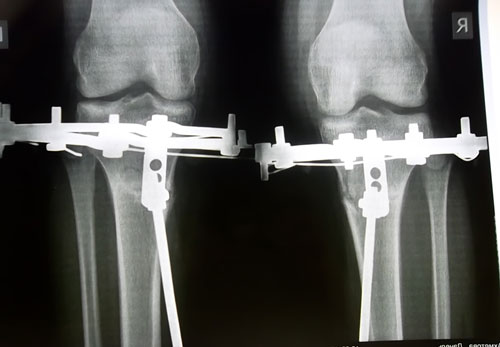

Дата операции 26 мая 2012г.

Рентгеновские снимки от 20.07.2012г.

Дата операции 26.05.2012г.

Дата снятия аппаратов 07.08.2012г.

Срок лечения 71 день.